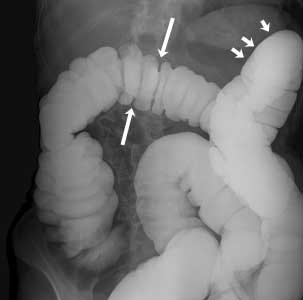

Enema de bario normal